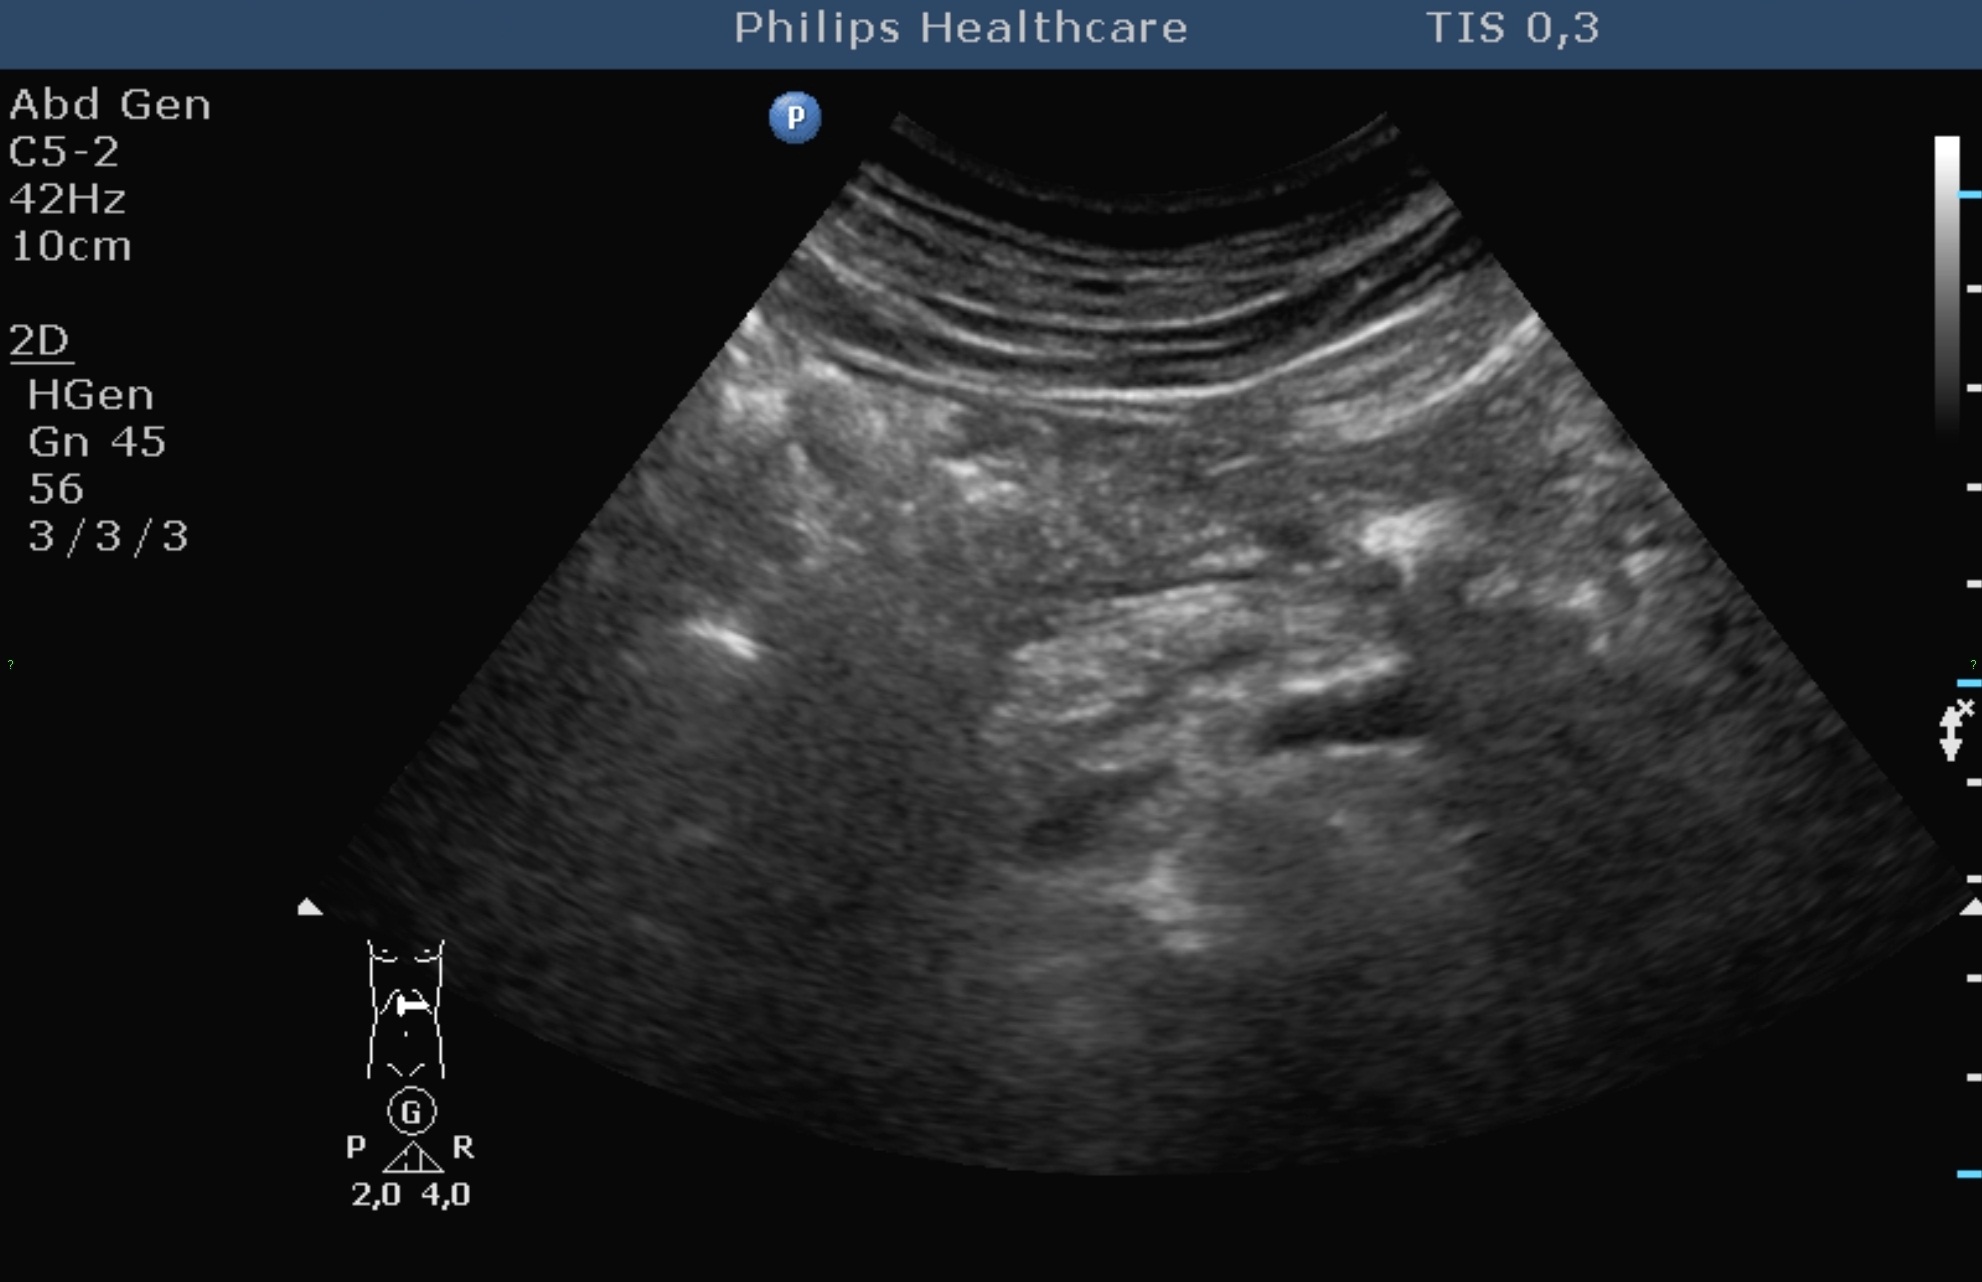

The echogenicity of the normal liver tissue is mildly hyperechoic (Figure 3) due to the intrahepatic connecting tissue structures, small veins, arteries and bile ducts (its echogenicity is principally comparable with the adjacent normal right kidney cortex, the liver has a bit hyperechoic structure than the right kidney, and its echogenecity is principally the same as the spleen's).

Figure 3: Normal liver, 2D US image

The portal vein and its branches have hyperechoic walls which can be easily differenciated in the liver structure. The walls of the hepatic vein branches have remarkable less echogenecity. The normal diameter intrahepatic bile ducts and the smaller liver arteries cannot be imaged and observed. The wall of the hepatic ducts and the main biliary duct (ductus choledochus) is also moderately hyperechoic. The hepatic hilum consists of the „double barrel” configuration (main biliary duct – portal vein, inbetween the cross-sectional view of the hepatic artery trunk) in the typical anatomical location, using an appropriate longitudinal plane.